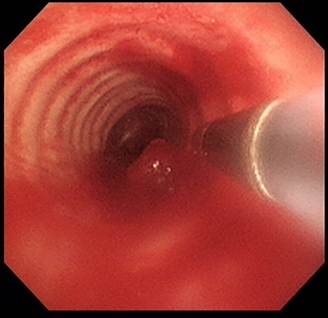

老先生近半年持續咳嗽,胸部電腦斷層檢查並未發現肺實質有轉移復發之病灶,一般止咳藥物也無明顯療效,後轉診至台大醫院新竹分院求診。經支氣管鏡檢查發現數顆氣管內腫瘤位於氣管及右側主支氣管,造成氣管近90%的阻塞。緊急安排支氣管內視鏡冷凍治療併腫瘤摘除後,老先生的症狀立即治癒,病理報告證實為大腸癌氣管內轉移。

台大醫院新竹分院胸腔內科林敬凱醫師表示,冷凍治療技術於1968年開始應用於氣管內的腫瘤治療,藉由液態氣體急速氣化造成相鄰組織的急速冷卻。除可造成腫瘤壞死,同時也將大塊腫瘤組織移除,迅速恢復氣管內的暢通。因治療時出血較少,對氣管內組織傷害較小,且可反覆執行於同一名患者,常為醫師對支氣管內腫瘤治療的第一選擇。